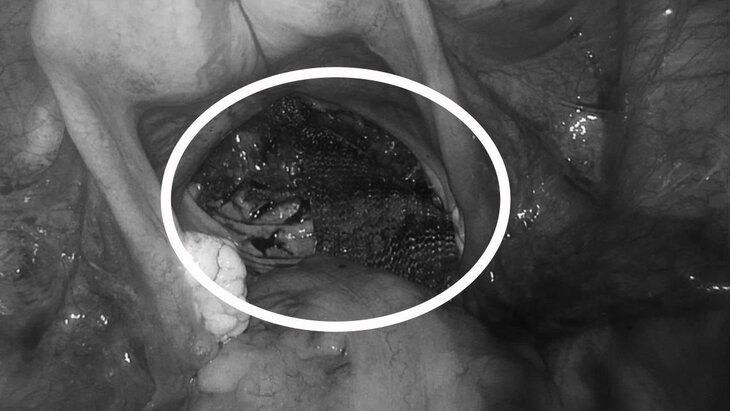

В больнице Наро-Фоминска спасли 40-летнюю женщину с осложнениям после травмы позвоночника. Пациентка в течение пяти лет страдала от выпадения прямой кишки, сообщает телеканал "360".

Как указано в сообщении, качество жизни женщины ухудшилось из-за патологии. Врачи обследовали ее и приняли решение о вмешательстве. Пациентке провели лапароскопию через четыре прокола.

"Мы произвели выделение прямой кишки и зафиксировали ее выпадающую часть специальной сеткой", – пояснил заведующий хирургическим отделением Альберт Тинис, добавив, что это позволило устранить основную проблему.